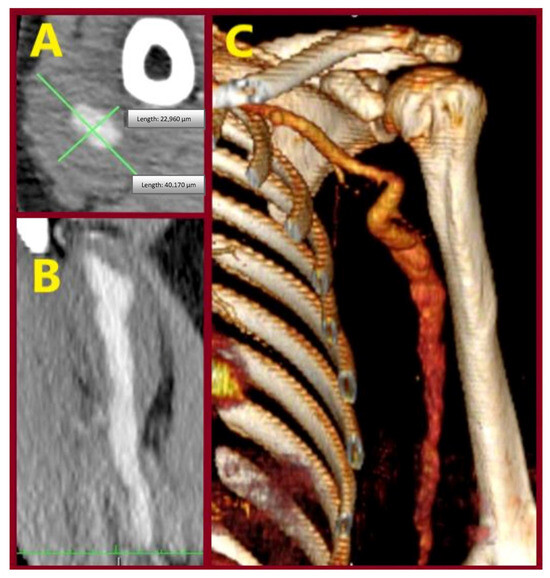

Idiopathic True Aneurysms of the Brachial Artery: A Short Case Series and Scoping Review

Background: Brachial artery aneurysms are a rare entity occurring sporadically at all ages. Common causes are trauma, infection, connective tissue disorders, genetic syndromes, immunosuppression, and a history of arteriovenous vascular access. Pseudoaneurysms are mainly of traumatic or iatrogenic origin. Idiopathic true brachial artery [...] Read more.

Background: Brachial artery aneurysms are a rare entity occurring sporadically at all ages. Common causes are trauma, infection, connective tissue disorders, genetic syndromes, immunosuppression, and a history of arteriovenous vascular access. Pseudoaneurysms are mainly of traumatic or iatrogenic origin. Idiopathic true brachial artery aneurysms are even scarcer, attributed to inherited susceptibility for aneurysm formation or to atherosclerosis. Due to the rarity of these aneurysms, we report our experience along with a current literature review. Methods: A retrospective search was conducted in the Vascular Surgery Department database of a tertiary referral center for vascular surgery, covering procedures from January 1991 to October 2025. Patients were included if they had undergone idiopathic true brachial artery aneurysm repair. Clinical records, operative details, imaging studies, and follow-up data were reviewed. We additionally provide a literature review regarding clinical presentation, signs, pathophysiology, diagnosis, and treatment of these aneurysms. Results: Amongst all procedures performed for aneurysmal repair, in the searched period, we identified three patients who met these criteria. All three underwent successful elective operations. Individual characteristics of the retrieved cases are reported. Conclusions: The open repair of true idiopathic brachial artery aneurysms is a technically simple approach that leads to satisfactory outcomes. Endovascular therapy is technically unfavorable in this type of aneurysm. Full article

Show Figures

Figure 1